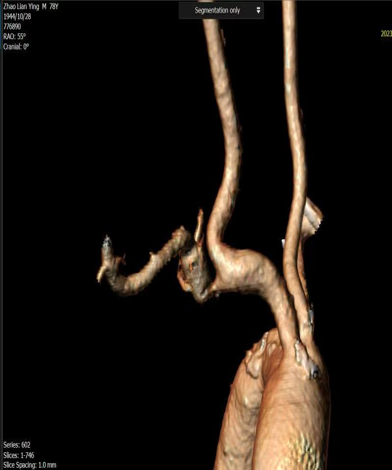

右锁骨下动脉与颈动脉开口狭窄(对吻支架技术):

对于头臂干分叉处病变,需要同时对右锁骨下动脉和颈动脉植入支架(对吻支架)。术前CTA重建确定了最佳角度,术中直接采用该角度进行造影和支架释放,确保了双支架的精准定位,避免相互影响。

图:CTA图像

图:术中CTA图像指导导丝导管方向